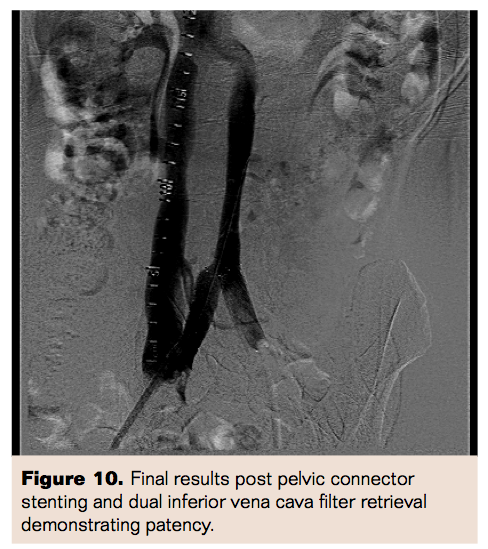

She was then brought back to the catheterization laboratory the next day for venography and her residual thrombus burden was assessed. Venography was performed with demarcation of the limits of residual thrombus and showed some improvement in blood flow. An 8 Fr, 30 cm therapeutic length Trellis device (Covidien Inc) was then advanced with the distal port in the left common iliac vein and proximal port in the left deep femoral vein. Trellis thrombectomy was performed for 10 minutes with a total of 10 mg of tPA administered. Thrombus material was aspirated. The therapy was once again repeated, from the left deep femoral vein to the left popliteal vein. Final images were obtained which showed marked improvement in blood flow. Her left lower extremity swelling along with symptoms of DVT significantly improved within 24 hours and she was discharged home after being started on warfarin oral anticoagulation therapy.